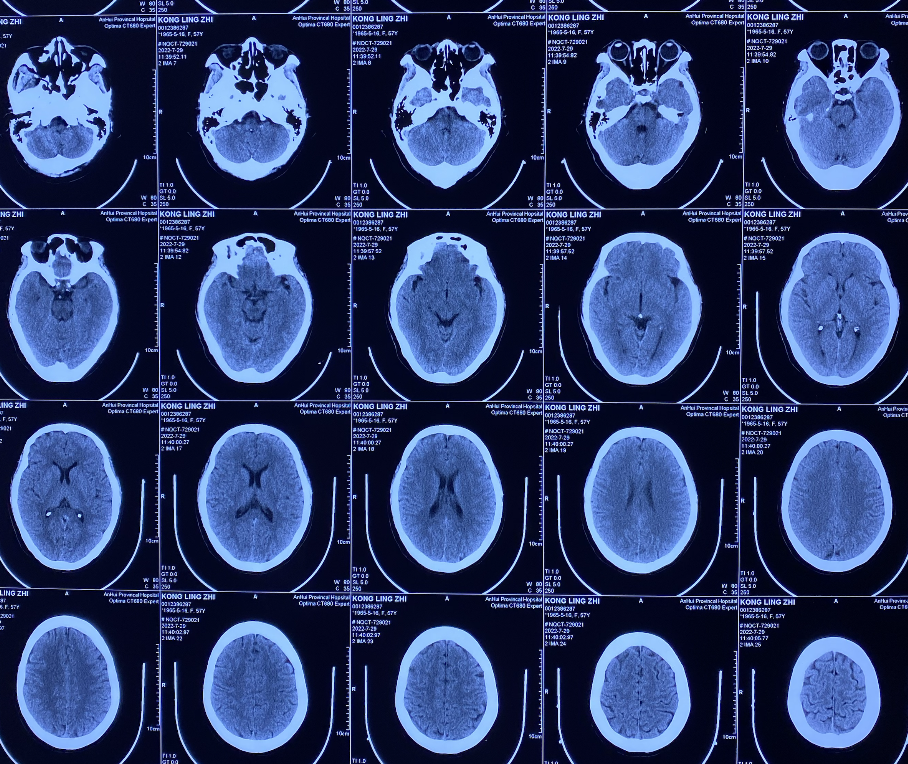

头颅CT

• 患者信息:女性,57岁,检查发现颅内动脉瘤1周。

• 现病史:患者一周前去体检时行头颅CTA检查发现颅内动脉瘤,无四肢麻木乏力,无明显头痛等其他不适主诉,为进一步治疗,来我院。发病以来,饮食睡眠及大小便正常,体重无明显增减。

• 既往史:高血压病史10余年,目前口服“氨氯地平”治疗,血压控制尚可;否认“糖尿病、心脏病” 病史,无肝炎、结核病史,无食物、药物过敏史。